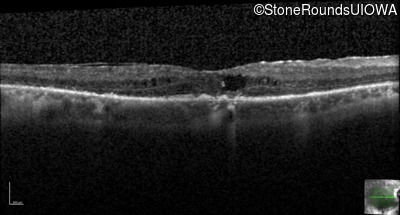

AR Retinitis Pigmentosa (IA1aiii)

Age at visit: 66 years

AR Retinitis Pigmentosa IFT172 Ala644Glu GCG>GAG Arg1284Stop CGA>TGA AR